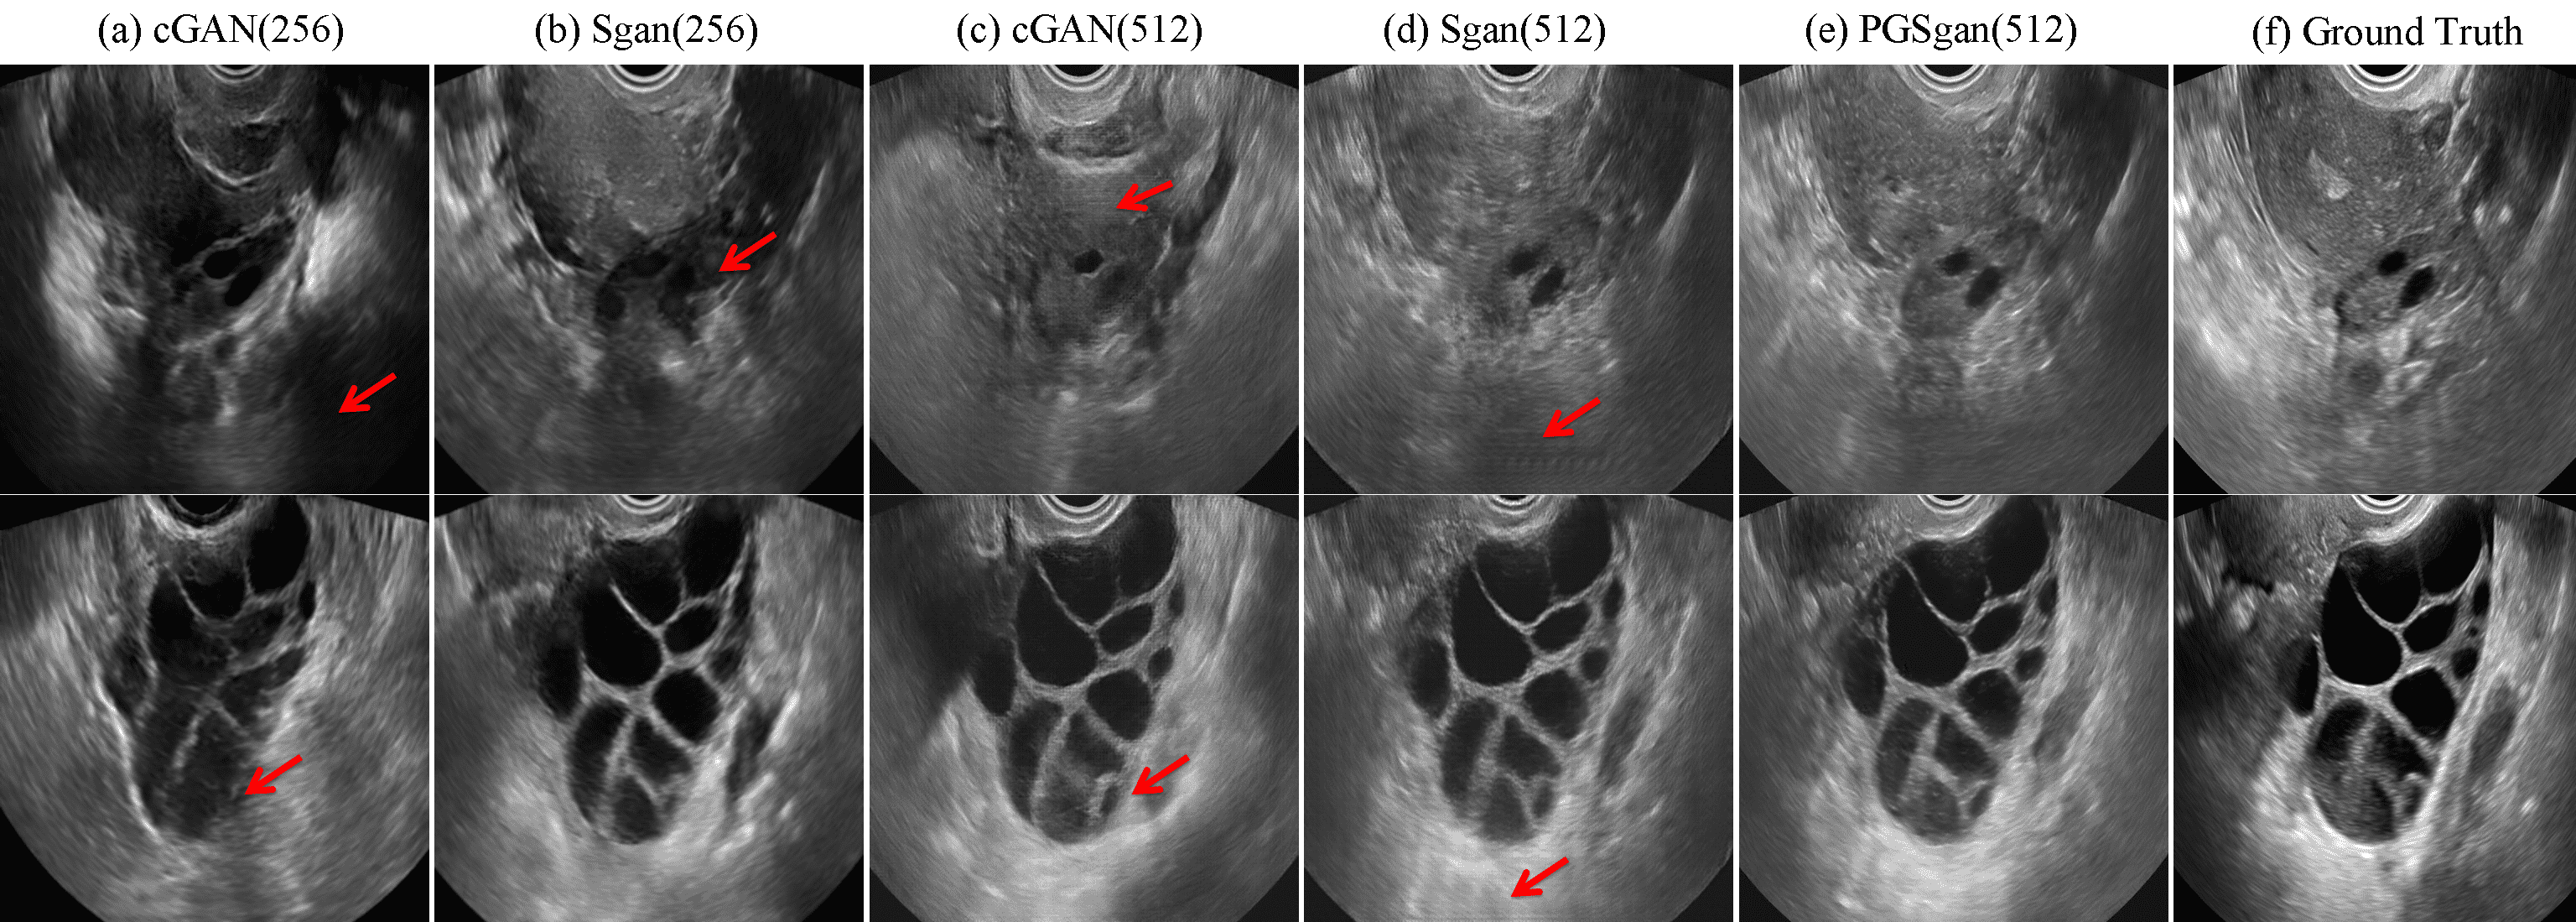

Refer to caption

Fig. 4: Visual comparison of some synthesized images from different methods at the resolution of 512×\times512.

Fig. 4 visualizes the comparison of generated US images from different methods. Some defects such as background distortion (a,b), checkerboard artifacts (c) and stretching effects (d) are denoted by arrows in Fig. 4. In contrast, our method generates more realistic synthesized images. Furthermore, our method enables not only synthesizing images from real labels but also being capable to generate images using edited labels (see Fig. 5). By this way, we can create high fidelity ovarian US images with various pathological morphologies. Table 1 further lists the numerical evaluation metrics, including Freshet Inception Distance (FID) [14], Kernel Inception Distance (KID) [15] and multi-scale structural similarity (MS-SSIM) [16]. 8.5 hours was needed for training the resolution of 256 and 16 hours for resolution of 512. For testing phase, it took only 0.07s for an image generation in GPU and 5.58s in CPU on average. Our method outperformes all other compared methods with regard to all metrics, which is mainly due to the employment of auxiliary sketch and progressive training scheme.